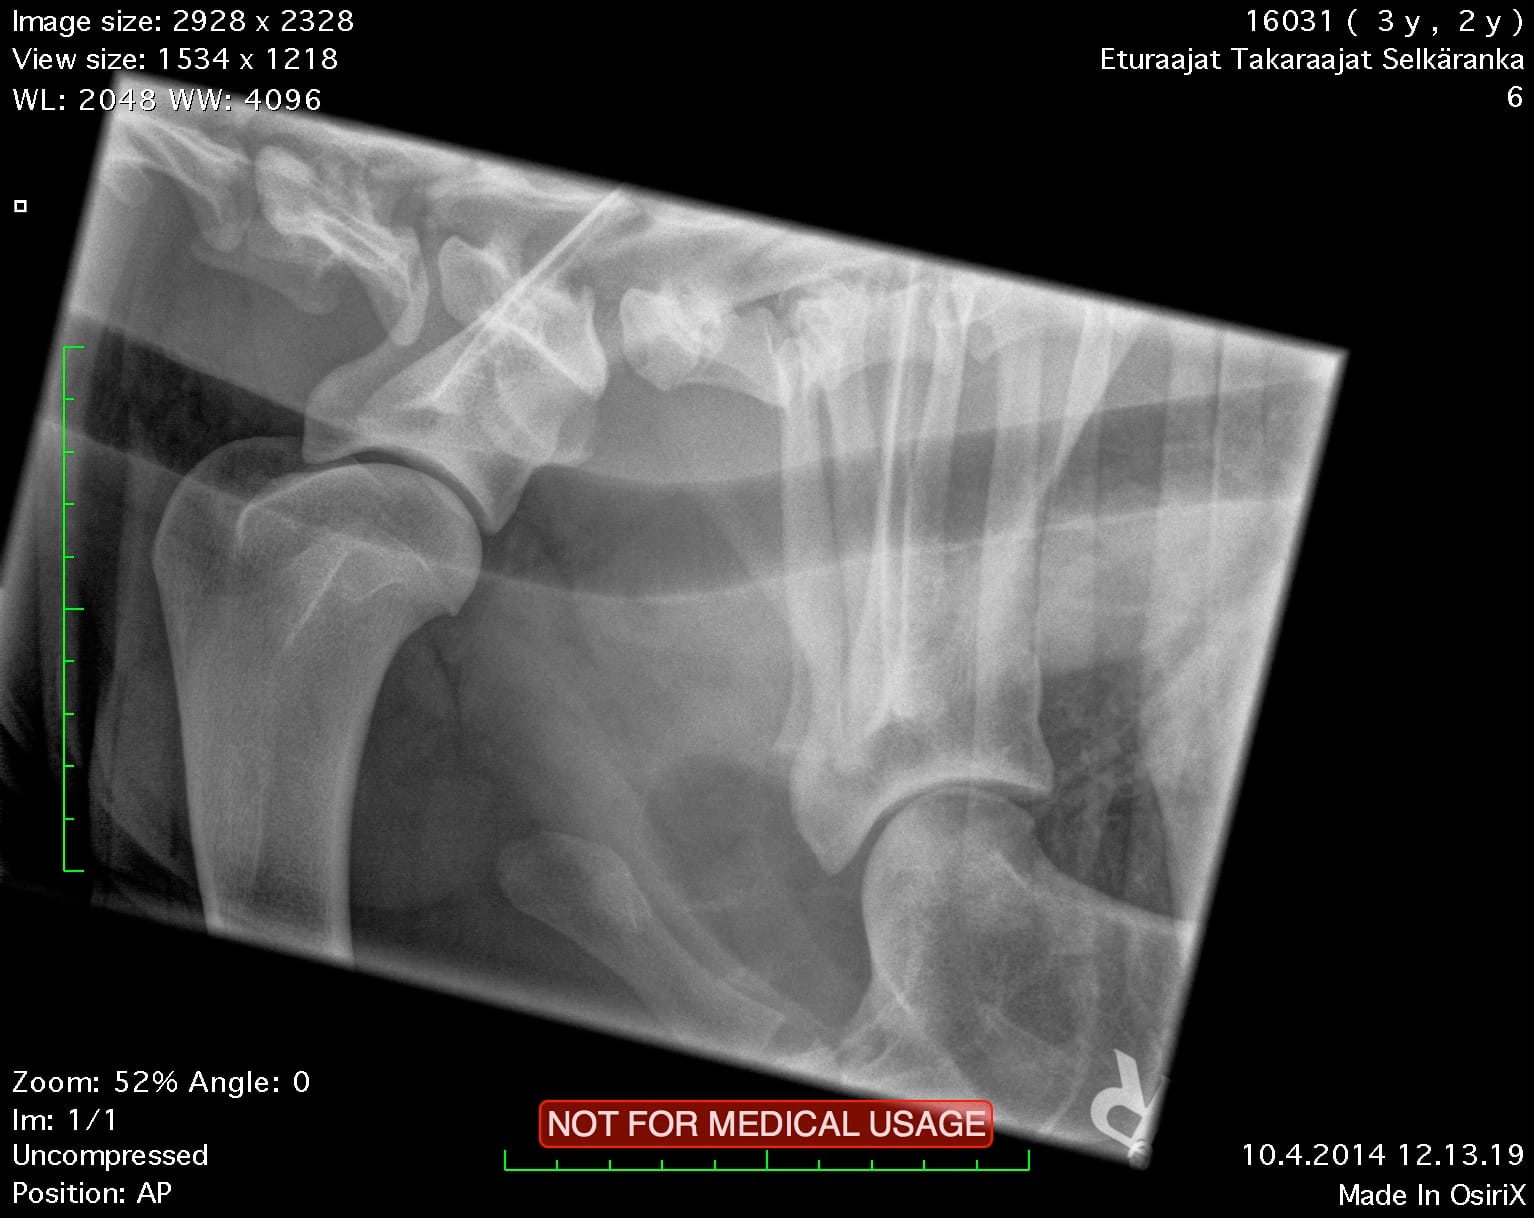

| Shoulders: | clear | |

| Spine: | SP0, LTV4 (8 lumbosacral vertebrae) | |